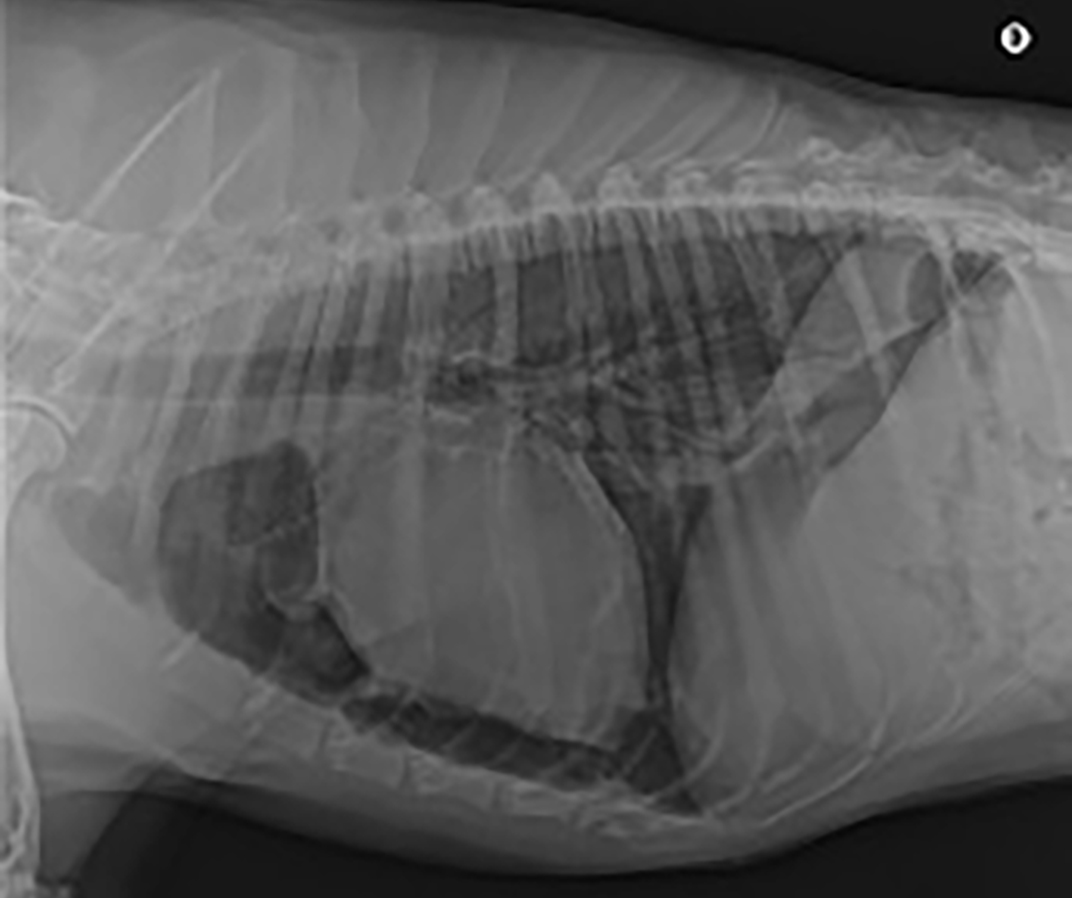

Un bilan traumatologique est réalisé. Le bilan sanguin (lactatémie, glycémie, hématocrite, protéines totales) est normal. Des POCUS thoraciques et abdominaux sont réalisés, sans anomalie à l’admission. Une radiographie du bassin ne montre aucune anomalie. Des radiographies thoraciques sont réalisées quelques heures après l’admission (figures 1, 2 et 3).

Aucune anomalie n’est visualisée au sein des structures extra-thoraciques. Au niveau des structures intrathoraciques, nous observons un discret pneumothorax ainsi que des contusions pulmonaires, plus marquées à droite. Nous observons également la présence de deux bulles pulmonaires, une de grande taille au niveau du lobe caudal gauche et une de taille moyenne au niveau d’un des lobes crâniaux (bulle non retrouvée sur la vue de face).

Figure 4 : Radiographie du thorax à l’admission, vue de profil droit légendée